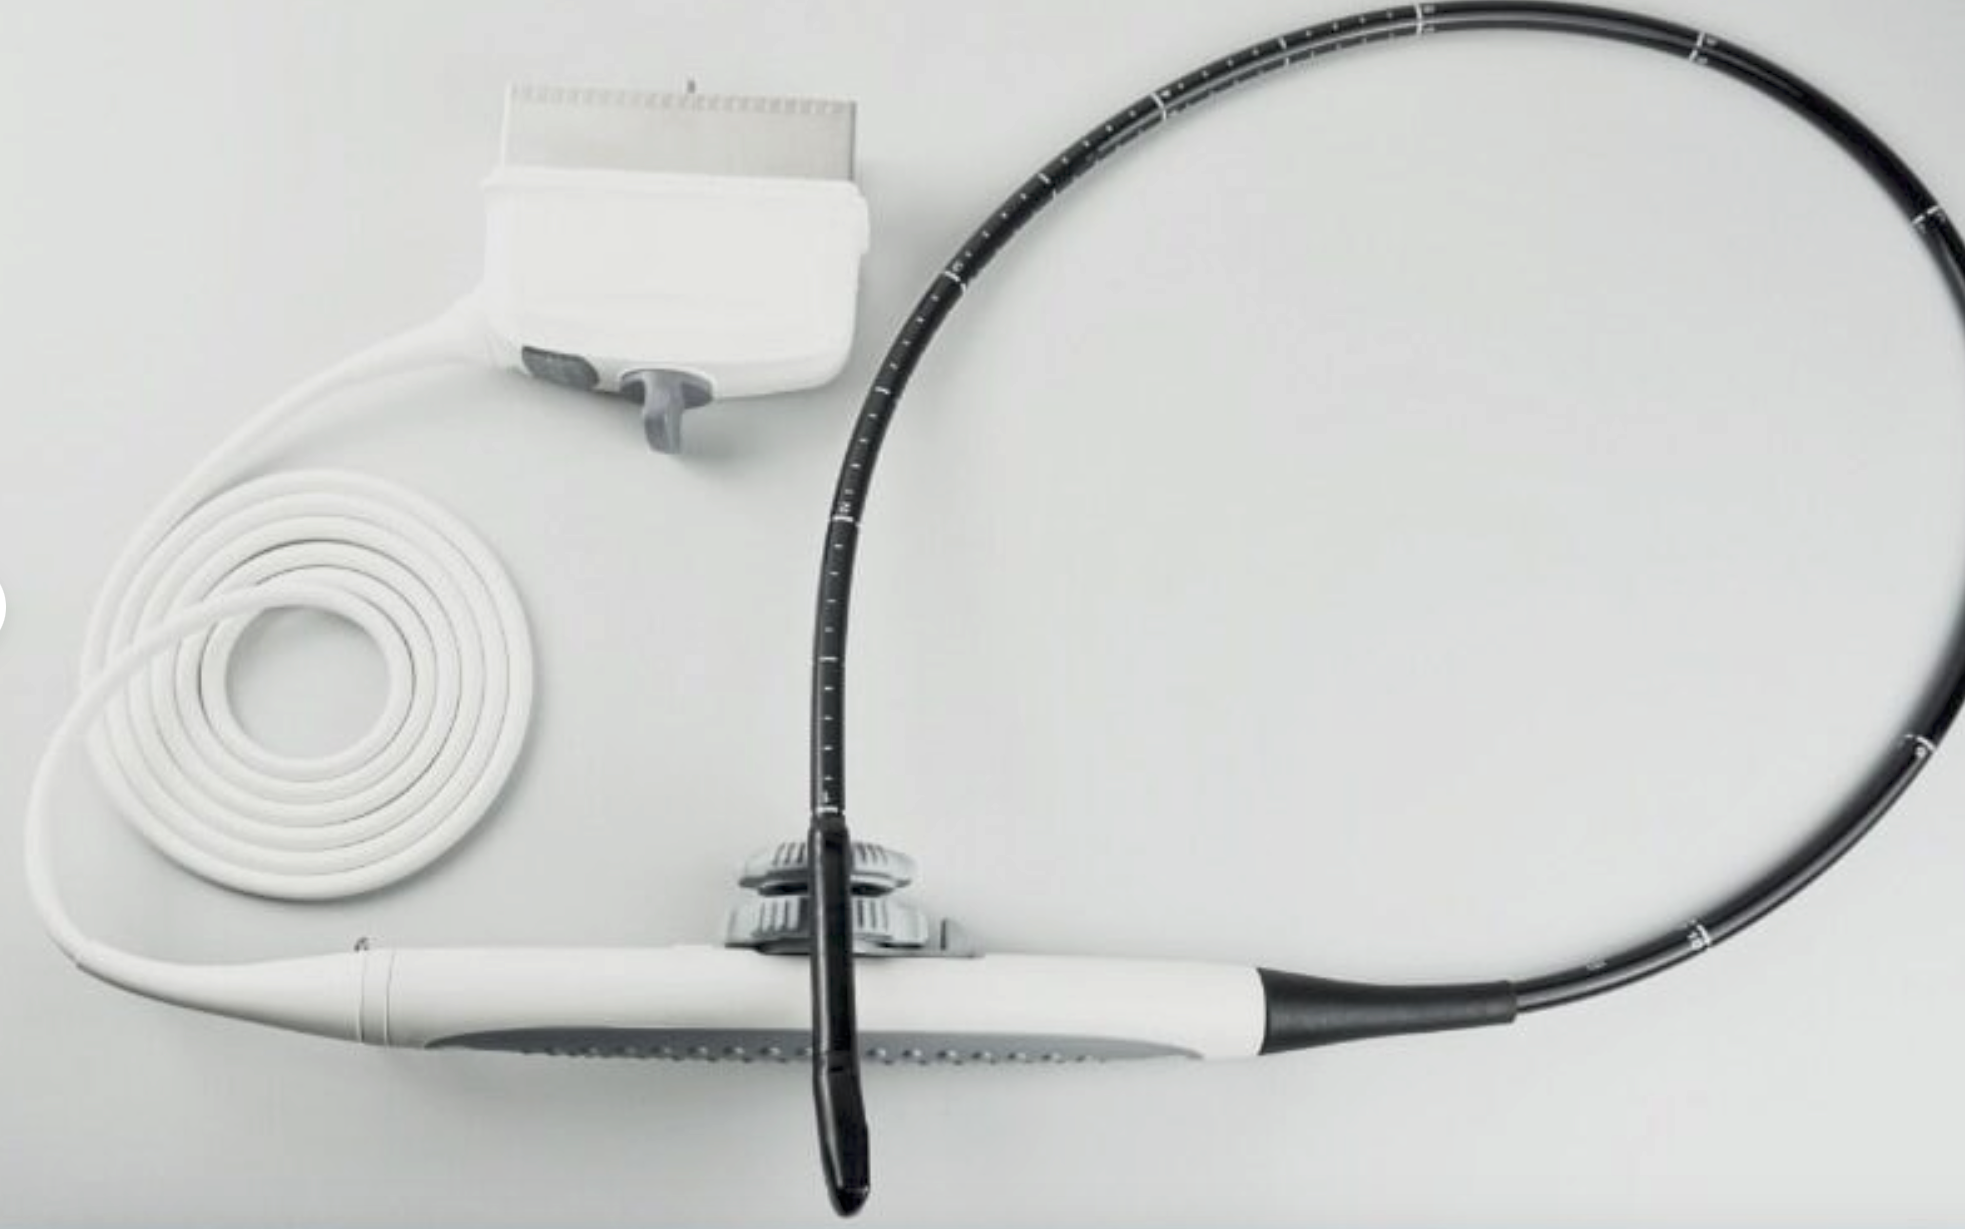

Probe 2: 7.5MHZ Transvaginal probe:gynecologic examination

This ultrasound scanner's dual probe system means that healthcare providers can easily switch between imaging modes. The convex probe is excellent for abdominal and fetal imaging, while the transvaginal probe allows for detailed pelvic examinations. Because of this flexibility, medical professionals can perform a wide variety of procedures without needing multiple machines. Therefore, hospitals can optimize their workflow and save valuable time.